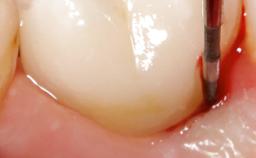

Maintenance of healthy peri-implant soft tissue as well as supporting peri-implant bone is an essential part of long-term success of implant therapy. An accurate maintenance protocol of peri-implant tissue health may prevent biological complications such as peri-implantitis. After the delivery of the prosthesis, patients should be followed up and clinical and radiological examinations should be performed on a regular basis to detect any etiological factors that may lead to such complications. This topic discusses properties of healthy and pathological conditions of peri-implant tissue, clinical and radiological examination methods of peri-implant tissue, as well as protocols for maintaining peri-implant tissue health.

- explain clinical and radiological examination methods to evaluate peri-implant tissue health